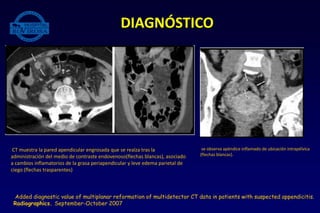

• TAC: alteraciones para apendicitis:

• Apéndice distendido con diámetro transverso mayor a 6-7 mm, por lo general de

ubicación retrocecal, siempre teniendo en cuenta las localizaciones menos frecuentes.

• Presencia de apendicolito.

• Engrosamiento parietal que realza con el medio de contraste endovenoso.

• Cambios inflamatorios periapendiculares.

• Adenopatías pericecales.

Reconstrucción coronal de apendicitis distal (flechs blancas) conapendicolito

(flecha transparente). Puntas de flecha muestran tercio proximal del

apendice)

CT muestra la pared apendicular engrosada que se realza tras la

administración del medio de contraste endovenoso(flechas blancas), asociado

a cambios inflamatorios de la grasa periapendicular y leve edema parietal de

ciego (flechas trasparentes)

se observa apéndice inflamado de ubicación intrapélvica

(flechas blancas).